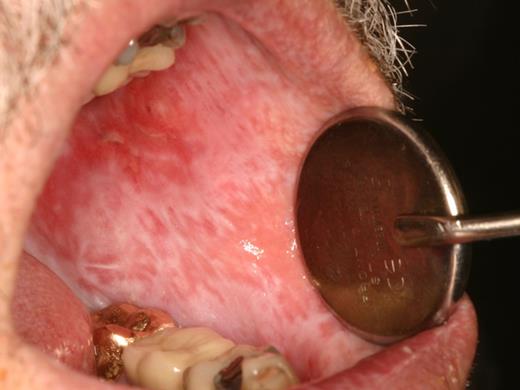

Oral mucosal cGVHD is characterized by lichenoid inflammation that can involve all intraoral sites, but particularly affects the tongue and buccal mucosa.8,13,14 Clinical signs include white hyperkeratotic reticulations and plaques, erythematous changes, and ulcerations, which can range from very limited disease with only mild reticulation to more extensive disease with painful ulcerations (Figures 1 and 2). Of note, the soft palate is infrequently affected, and cGVHD changes rarely extend posteriorly to the oropharynx (Figure 3).13 The lips are also a frequent site of involvement, demonstrating the same changes observed intraorally, and can be a source of significant discomfort (Figure 4).

The primary symptom associated with oral mucosal cGVHD is sensitivity to otherwise normally tolerated foods, drinks, and oral hygiene products, with most patients reporting little if any oral discomfort at rest. Foods and drinks that are consistently reported by patients as being painful include those that are spicy (eg, even a very small amount of pepper), acidic (eg, fruits, salad dressing), and hard/rough/crunchy; however, in some patients there is universal sensitivity such that oral intake becomes severely restricted. Although symptoms are generally worse with more severe clinical manifestations, this is not universally true, and patients with only reticular changes may be as or more symptomatic than patients with ulcerations.13 When there are prominent reticular changes affecting the buccal mucosa, patients may report a sensation of mouth tightness and a reduced ability to open the mouth (Figure 5). This should be differentiated from oral tightness because of primary sclerotic cutaneous cGVHD or secondary to mucosal scarring (see “Sclerotic disease”).

cGVHD of the buccal mucosa with extensive and thick hyperkeratosis making the mouth feel “tight” with limited opening.